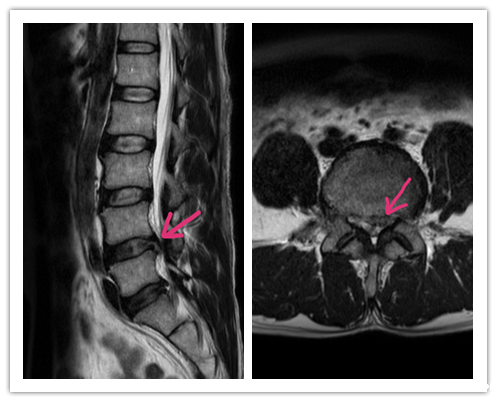

几经辗转,张先生到我院骨科门诊求医,经腰椎MRI检查发现腰椎间盘突出(L4/5),得知我院骨科能用椎间孔镜微创手术治疗这个疾病,欧先生欣喜万分。

(腰4/5椎间盘突出)